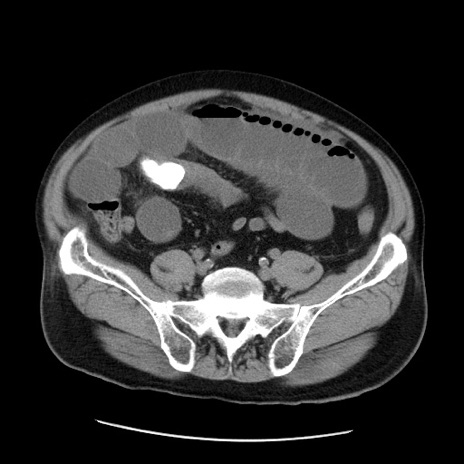

症例20(横断像)

【症例】 60歳代男性

【主訴】 腹部膨満、嘔吐

【現病歴】5日前頃より倦怠感を認め食事量減少し4日前の朝嘔吐、食事摂取困難となった。 3日前近医受診し点滴施行され整腸剤などを処方された。 当日他院を受診し、腹部膨満著明、炎症反応の上昇(CRP10.8、WBC11200)あり、紹介受診となる。

【身体所見】 意識JCS1 受け答えがはっきりしないBP 111/57mHg、 P 67bpm、、BT35.2°C、SpO2 97%(RA)、 腹部:膨隆、打診で鼓音あり、全体的に圧痛有り、腸蠕動音(-)、反跳痛ははっきりせず。

【データ】WBC 11400、CRP 14.20